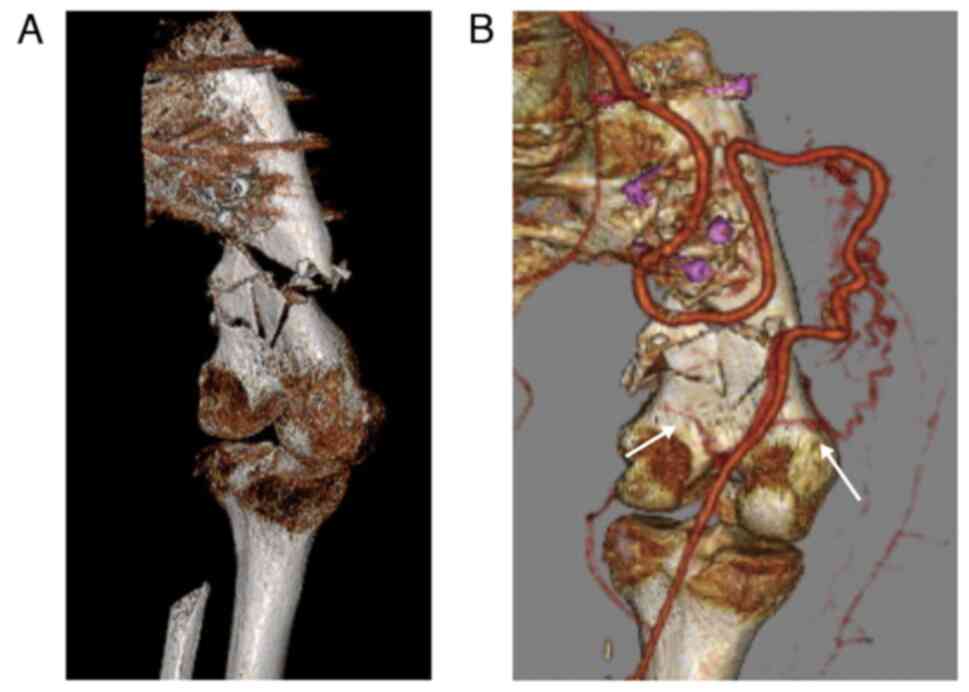

Reconstructed bone fracture 28 years after hip rotationplasty for Ewing sarcoma: A case report

Hip rotationplasty is a surgical method used to treat malignant tumors of the proximal femur. A 52‑year‑old woman, who underwent hip rotationplasty for Ewing sarcoma of the proximal left femur at the age of 24, fell and hit the left buttock. The patient was then admitted to the Department of Orthopedic Surgery, Graduate School of Medicine, University of the Ryukyus. Radiography and computed tomography (CT) revealed a comminuted fracture of the reconstructed bone distally. The patient underwent open reduction and internal fixation (ORIF) and external fixator. External fixation was removed 1 month after the surgery. At two years after surgery, at the latest follow‑up, bone union was confirmed by 3‑dimensional CT. The combination of ORIF and temporal external fixation was effective for the reconstructed bone fractures after hip rotationplasty.

Figure 3

Figure 4